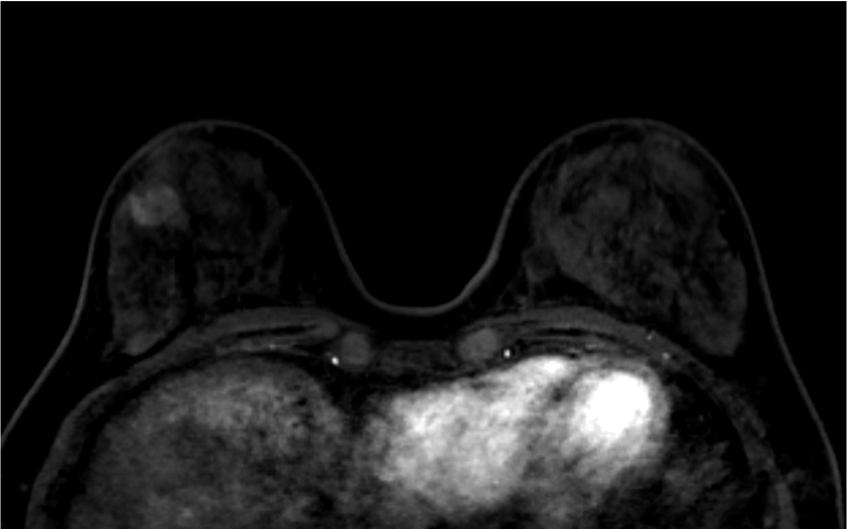

4. ダイナミックMRI (造影前 早期相 遅延相)

早期相で、乳腺の辺縁にBPE(矢印)を認めるが、その範囲は広くなくmildと判定する。乳癌の病変は、早期相から急速に造影され、遅延相でwash outがみられる。BPEは、遅延相で拡大し増強している。

5. Ultrafast DCE

乳癌の病変は、超早期(10相目: 造影剤注入32.5秒後)から急速に造影されている。背景乳腺は超早期では、ほとんど造影されていないが、17相目では軽度増強されている。

6. 造影後高分解能画像

乳癌の病変の形態は、不整形で、rim 状の造影域を認める。高分解能画像では形態的な性状を鮮明に観察できる。